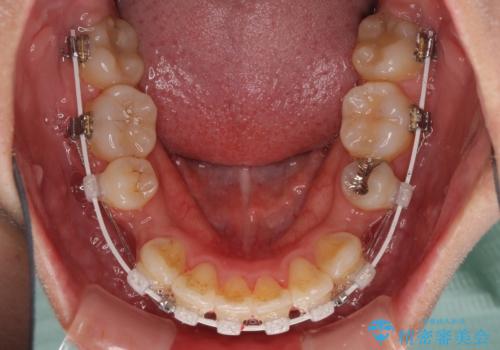

叢生解消のため、上下左右第一小臼歯4本を抜歯し、ワイヤー装置にて矯正治療を行うこととしました。

半年ほどで前歯のデコボコは改善され、汚れの溜まりやすさは解消されました。

抜歯スペースを閉じるために期間がかかりましたが、当初予定通り2年強で終えることができました。